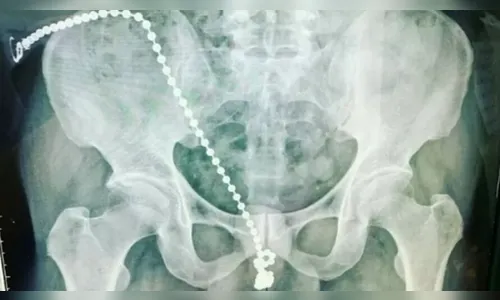

Um homem foi levado às pressas para o Hospital Shuang-Ho, da Universidade Médica de Taipei, Taiwan, sentindo fortes dores no pênis, que ele descreveu como “choque elétricos”. Nesse momento, os médicos constataram que ele havia introduzido uma corrente de bolinhas de metal na uretra para aumentar o prazer durante a masturbação. As informações são do UOL.

A equipe médica que atendeu o homem informou que a corrente introduzida impedia que o paciente fosse ao banheiro. Por conta das fortes dores, ele ficou com medo de removê-la e se machucar ainda mais.

O urologista Gao Weichang, que atendeu o homem, informou em uma entrevista coletiva que “o paciente não sabia como remover a corrente em casa. Ele já estava ferido e a corrente, presa. Mas se ele tentasse retirá-la, toda sua uretra poderia ter sido danificada”.

Ele também acrescentou que, em uma condição normal, a corrente teria deslizado para fora. Porém isso não aconteceu porque a uretra do homem estava apertada por causa da tensão.

Para removê-la, os cirurgiões tiveram de abrir o pênis do homem para desfazer nó que havia se formado na corrente. Depois, reconstruíram a uretra do paciente em um procedimento complexo, mas bem-sucedido.